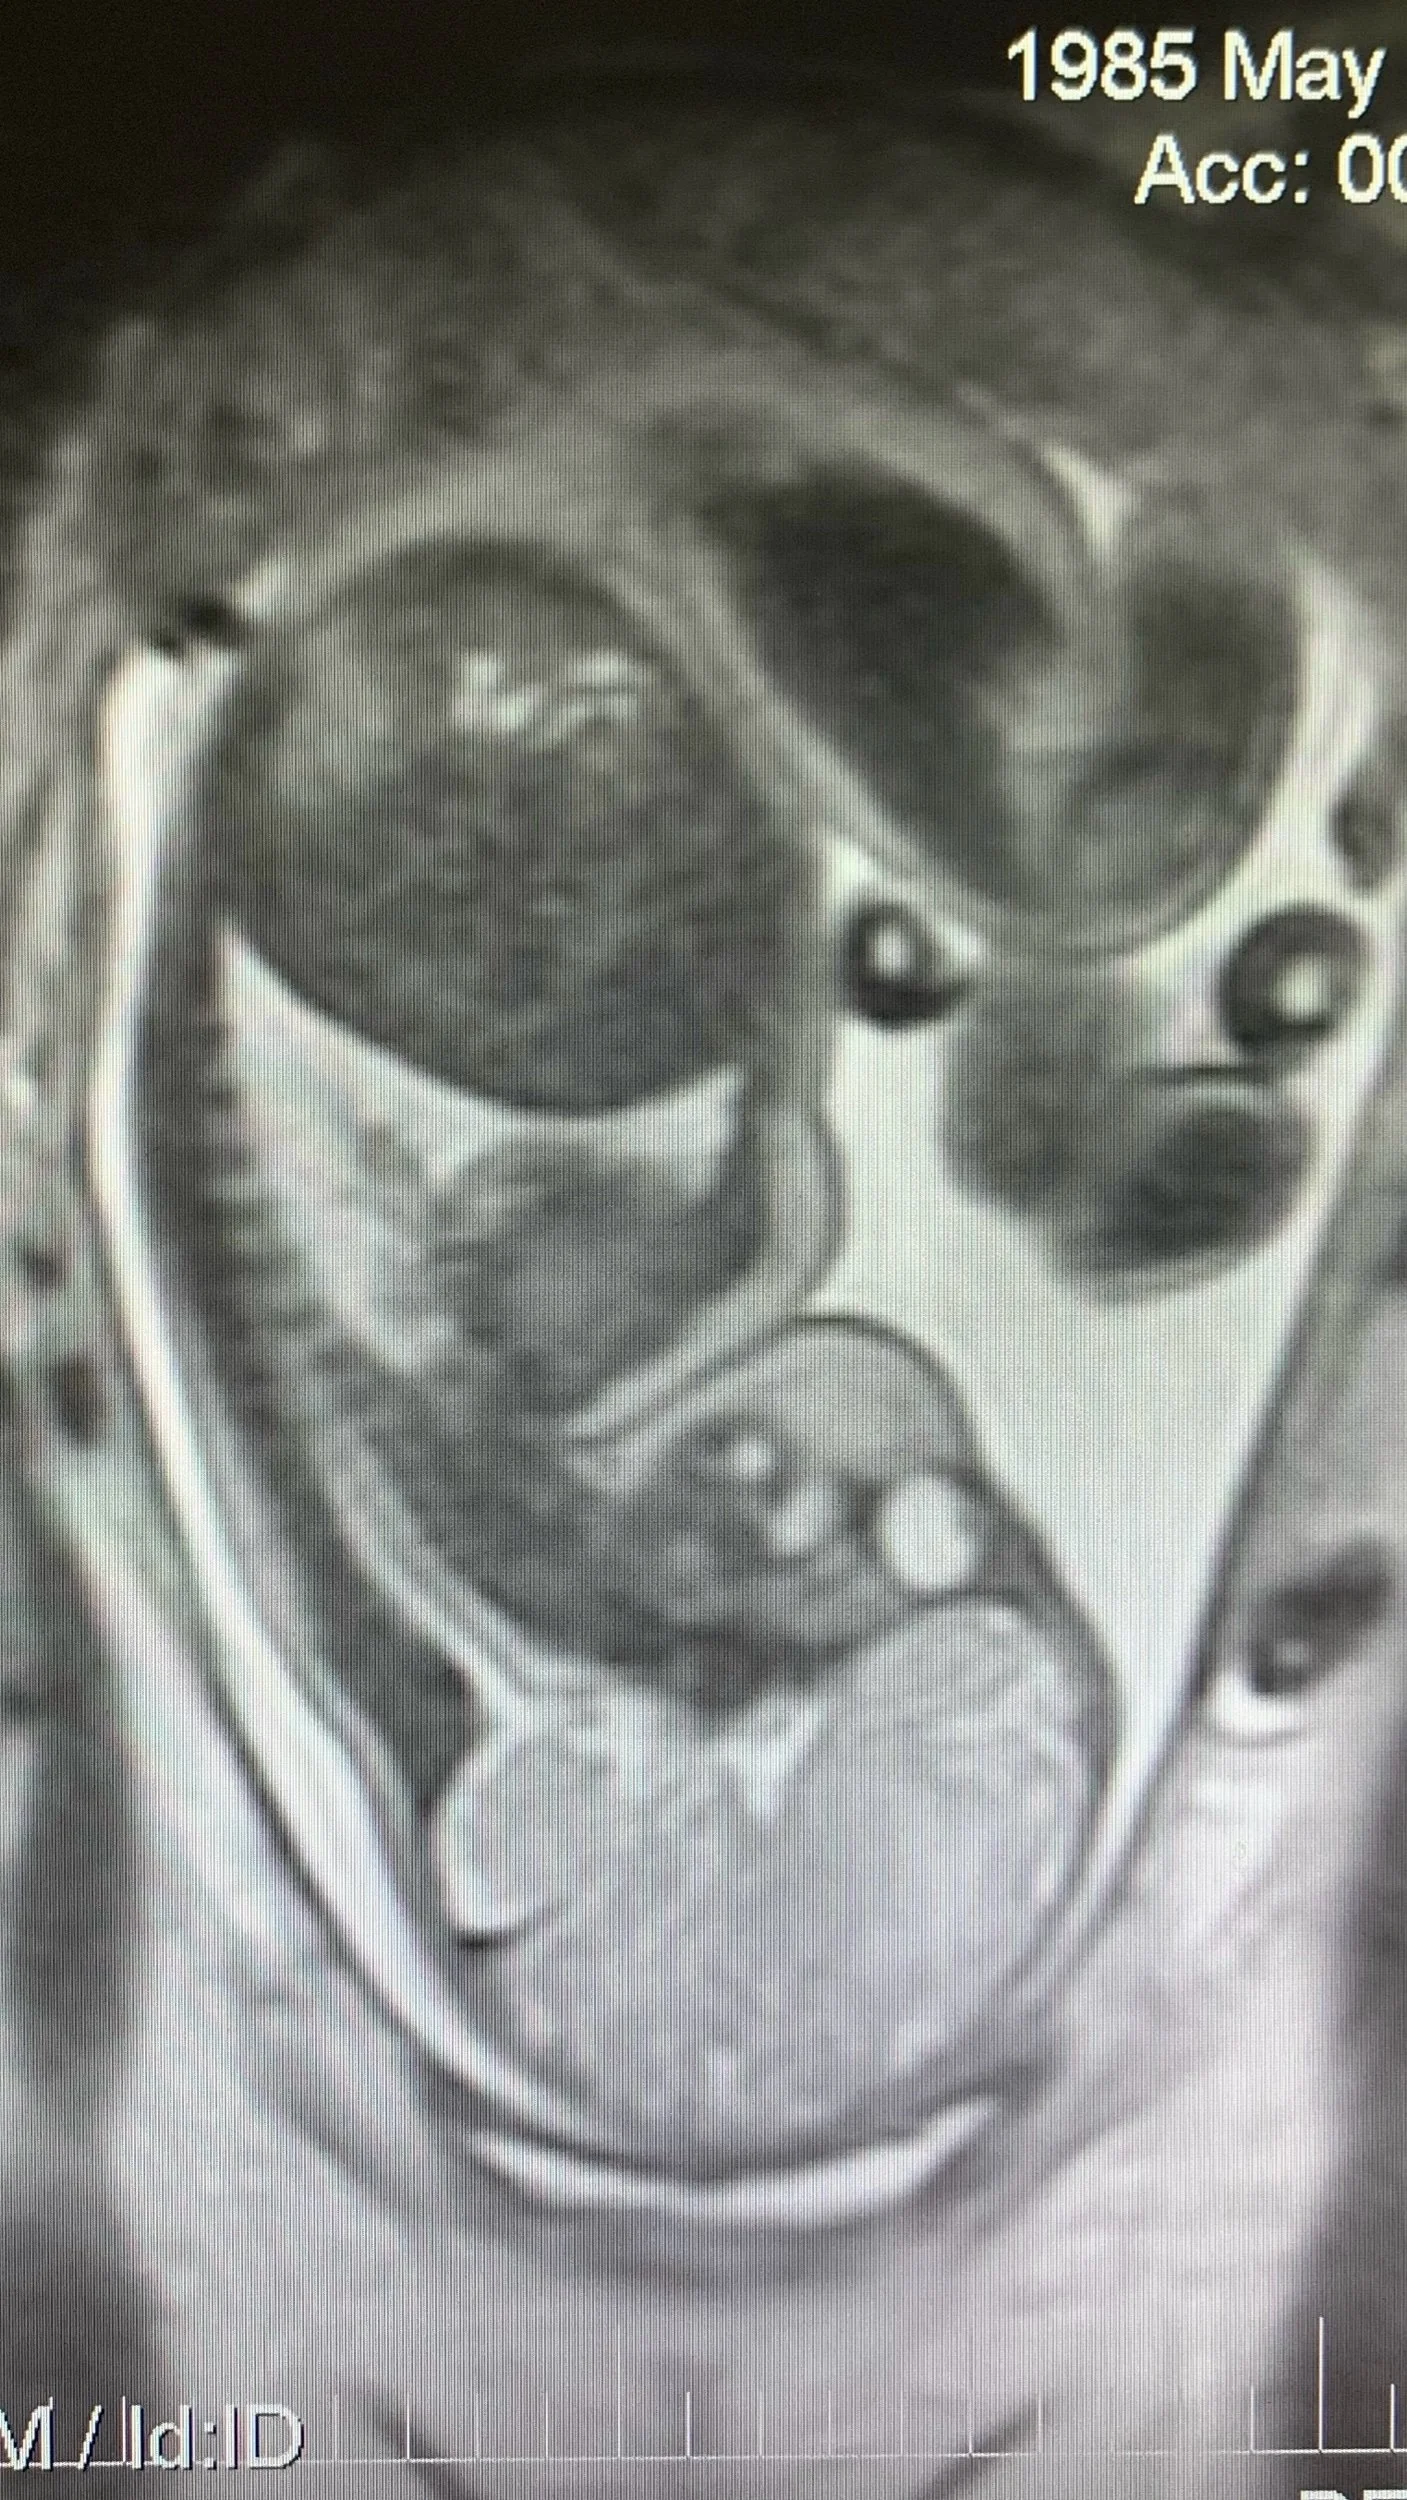

Fetal MRI - Emily

Emily - Fetal MRI, 2022

Acrylic on Canvas, 24” x 36”;

(Based on the fetal MRI below)